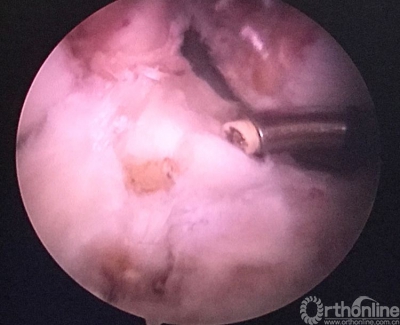

现等离子刀头所指处应该为正确的内口定位,原内口与此处相距较远。

现等离子刀头所指处为外侧半月板前角游离缘。左下方2个等离子刀烧灼处为原内口及准备返修的内口。